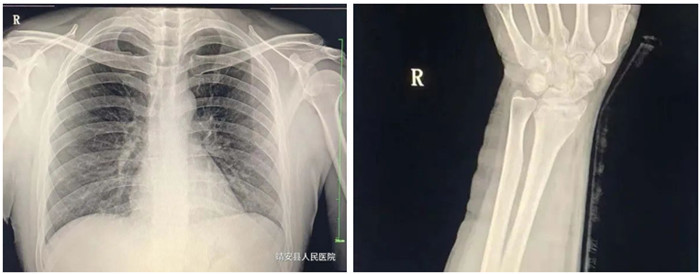

適應(yīng)癥:骨齡檢查、先天性發(fā)育異常、骨缺血性壞死;骨質(zhì)疏松、骨髓炎、骨腫瘤、骨關(guān)節(jié)創(chuàng)傷、骨關(guān)節(jié)結(jié)核、骨關(guān)節(jié)炎性病變、軟組織病變等疾病。

3.胸部

適應(yīng)癥:氣管支氣管病(支氣管結(jié)石及異物等);肺部病變(先天性發(fā)育異常、炎癥、結(jié)核、腫瘤等);縱膈病變(氣腫、血腫、腫瘤與囊腫等)。

普愛(ài)醫(yī)療PLX8500D數(shù)字化醫(yī)用X射線攝影系統(tǒng)(動(dòng)態(tài)DR)具有動(dòng)態(tài)、靜態(tài)圖像采集兩種攝影方式。17*17動(dòng)態(tài)大平板,900W高清像素,可以更有效覆蓋檢查范圍、降低檢查所需時(shí)間和曝光,從而確保提升影像檢查效率,有效避免廢片、漏診、誤診、二次拍攝、多次重復(fù)曝光等不良隱患情況的發(fā)生。采用超寬34寸液晶顯示器,解放雙屏雙工作站的束搏,實(shí)現(xiàn)采集圖像和回放圖像并列顯示,使臨床圖像效果對(duì)比更直觀,操作更方便快捷。